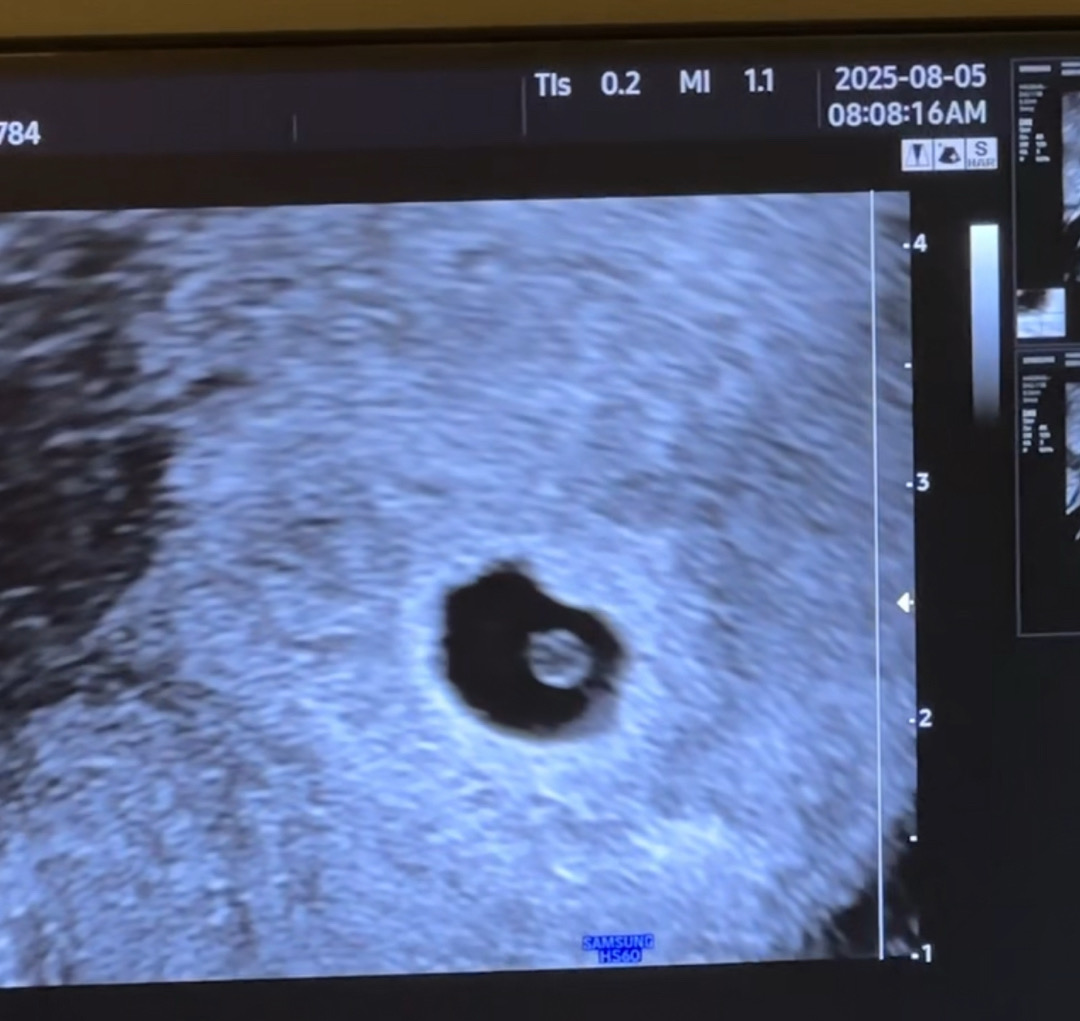

7월 14일 2차 인공수정 후 7월 29일 1차 피검422 8월 5일 오늘 2차 피검 9214 아기집 0.88cm이고 난황도 보고왔어요~~ 5주 0일로 알고갔는데 5주 1일차로 당겨졌구요 다 잘크고 잇구나 안심하고 좋아했는데 갑상선 수치가 6.85로 높대요 ㅠㅠㅠ 원래 2.5이거나 높아도 4까지라는데 ㅠㅠ 걱정되네요 흑